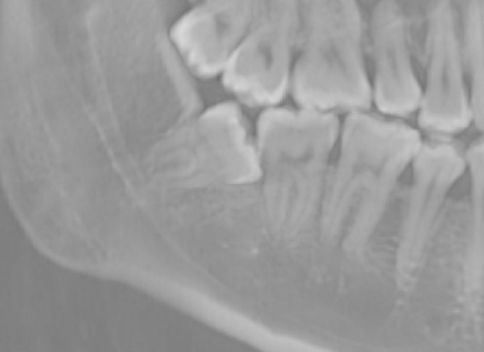

X光檢查和電腦斷層掃描:

這些檢查可以幫助醫師更精確地了解患者的骨質密度和位置,以便進行更精確的手術規劃。